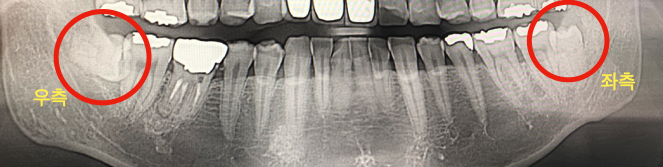

저희 경우에는 사랑니가 아랫니에만 두 개 있었고 좌측은 일반, 우측은 수평 매복이었습니다. 엑스레이랑 CT를 찍은 후 결과를 보시더니 여기에서 충분히 발치가 가능한 경우라며 바로 발치를 하겠느냐고 물어보시더라고요. 어차피 계속 아플 거면 한번 아프자 하고 바로 원한다고 했더니 정말 빠르게! 발치를 해 주셨습니다.